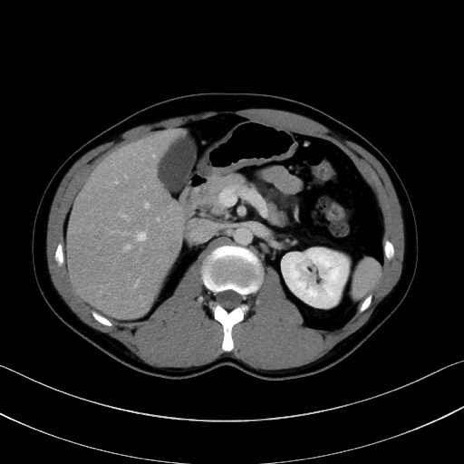

【症例】20歳代 男性 スクリーニング

■起始:典型的には腹腔動脈幹(celiac trunk)から左胃動脈・総肝動脈とともに三分岐し、脾動脈は左後上方へ向かう。

■走行:膵上縁または膵実質背側を蛇行しながら左方へ進み、膵尾部近傍で脾門へ至る。蛇行の程度は個体差が大きい。

■終枝:脾門部で複数の終末枝に分かれ、上極・下極枝や脾門枝群を形成する。胃短動脈群や左胃大網動脈はしばしば脾動脈から分岐する。